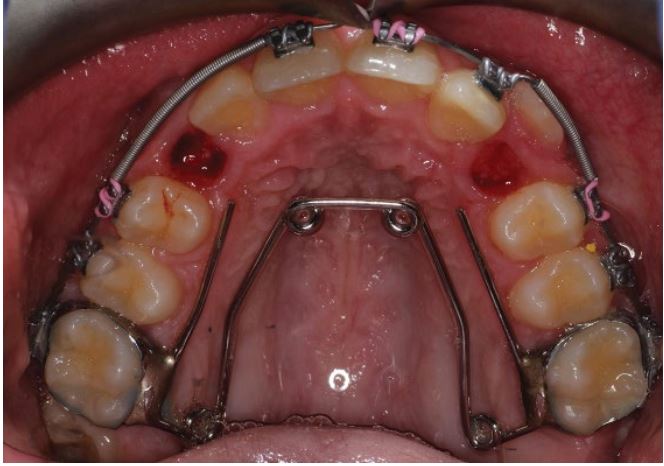

Cho bệnh nhân đeo thun tam giác 2 bên (thun 3/16”; 4.5 oz) móc từ R5 trên đến R4 + R5 dưới để hỗ trợ chỉnh khớp sớm và ngăn phản lực lún khi kéo R23 xuống.

4 tuần sau, tháo Quad-helix vì có tình trạng cắn chéo do nới rộng quá mức. Bệnh nhân được cho đeo thun cắn chéo (thun 3/16”; 4.5 oz) móc từ mặt ngoài răng cối trên đến mặt trong răng cối dưới.

Cắn chéo đã được điều chỉnh.

Gắn mắc cài R13, đi một dây phụ 014 NiTi và giữ nguyên dây chính.

Giữ nguyên lò xo giữ khoảng R33. Cho bệnh nhân đeo thun tam giác (3/16″; 4.5 oz) móc từ R4 hàm trên đến R4 + R5 hàm dưới để chỉnh khớp và tránh phản lực khi kéo R13.